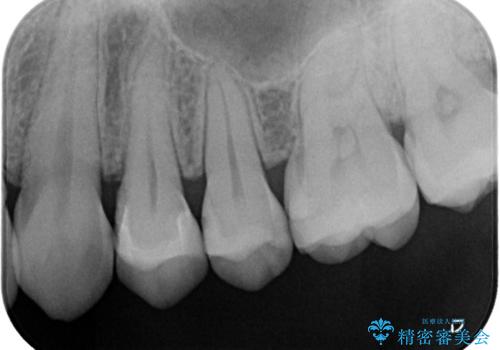

- 主訴:左上真ん中らへんの歯が欠けてしみるので治したい

左上4近心に実質欠損を認め、遠心から咬合面にかけてはCR修復が施されていたため、MODインレー窩洞としました。

インレー接着操作時はラバーダム防湿を行っています。